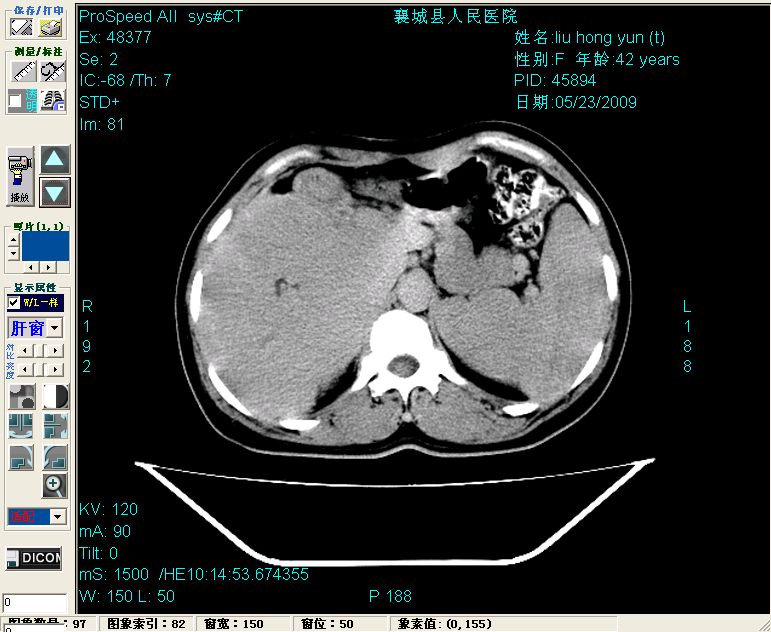

增强:

平扫左肝外叶体积显著减小,左肝外叶见多房囊性低密度区,左肝实质及右肝前叶浅表实质呈低密度改变,左肝及右肝前叶胆管扩张,脾大

增强动脉期前述低密度区轻度早其强化,门脉期强化程度显著增高,延期扫描强化程度下降,但仍为相对高密度影

2左肝及右肝前叶表现考虑胆囊摘除术后所致的肝动门脉瘘形成,慢性纤维组织炎性增生.不完全除外左肝胆管细胞癌

1)肝内胆管结石,胆总管末端结石伴肝内胆管扩张。2)肝左叶及肝右叶前段增强前后之异常表现,考虑炎性改变,不排除胆管细胞癌。

1)肝内胆管结石,胆总管末端结石伴肝内胆管扩张。2)肝左叶及肝右叶前段增强前后之异常表现,考虑炎性改变,不排除胆管细胞癌。3)脾大。